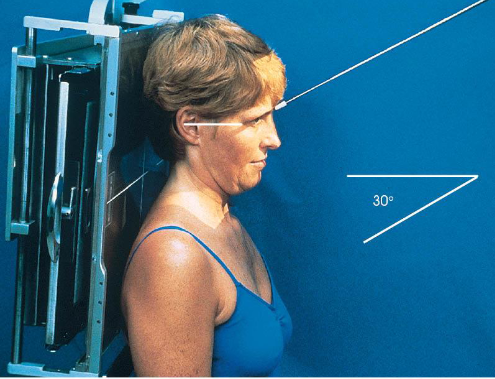

AP axial (modified Towne) zygomatic arches

patient position:

upright or supine

part position:

MSP perpendicular to midline

OML perpendicular to IR

may use IOML if patient can’t flex neck enough

increase in CR angle

respiration suspended

CR:

OML: 30 degrees caudad, enters glabella 1 inch above the nasion

IOML: 37 degrees caudad

collimation:

1 inch beyond the lateral sides of the face, superiorly to the top of the forehead, and inferiorly to the chin

AP axial (modified Towne) zygomatic arches image criteria

both zygomatic arches, free of superimposition

no overlap of arches by mandible

no rotation

symmetric arches

arches projected lateral to mandibular rami